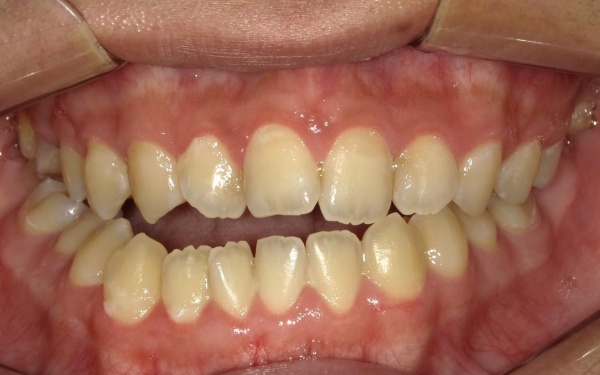

10代男性 顎変形症が原因で下顎がずれて非対称になっていた噛み合わせをサージェリーファースト法を併用した矯正治療で改善した症例

ご相談内容 「顔と顎がゆがんでいて、見た目が悪くしゃべりにくいのが気になる。また、前歯が噛み合っていないため、食べ物を噛み切ることができない」とご相談いただきました。

カウンセリング・診断結果 拝見したところ、骨格の問題により下前歯が上前歯より前に出ている前歯部反対咬合と、前歯が開いて噛み合わないオープンバイトが認められました。

さらに、下顎の骨が右方向にずれて上下の歯が噛み合う面が斜めになっていることで、顔面の非対称も見られます。

これらは顎変形症と呼ばれる状態で、現在は食べ物をしっかりと噛む機能が大きく制限されているうえ、発音や見た目に悪影響が出ていました。

治療前

治療前画像 治療前画像 治療前画像 治療前画像 治療前画像 治療前画像